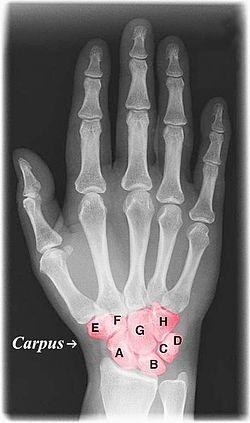

Labelled image showing the eight carpal bones.

The carpal bones are the eight small bones that make up the wrist (or carpus) that connects the hand to the forearm. The term "carpus" is derived from the Latin carpus and the Greek καρπός (karpós), meaning "wrist". In human anatomy, the main role of the wrist is to facilitate effective positioning of the hand and powerful use of the extensors and flexors of the forearm, and the mobility of individual carpal bones increase the freedom of movements at the wrist.[1]

The eight carpal bones may be conceptually organized as either two transverse rows, or three longitudinal columns.